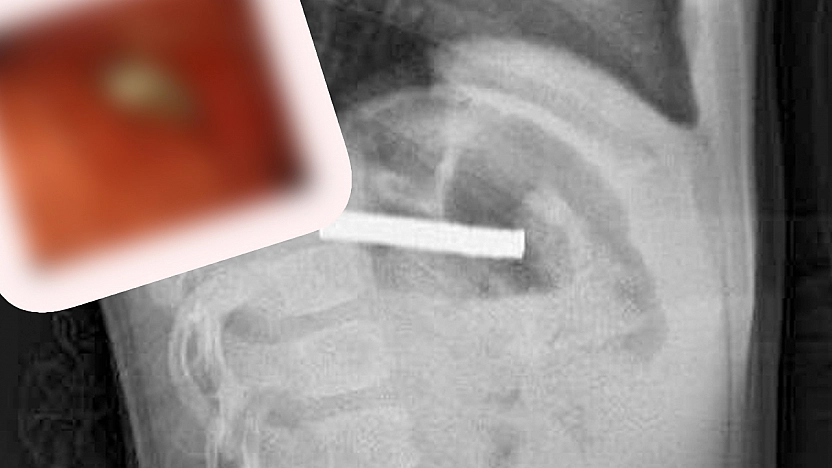

Elazığ’da 3 yaşındaki çocuğun midesinden çıkanlar şok etti